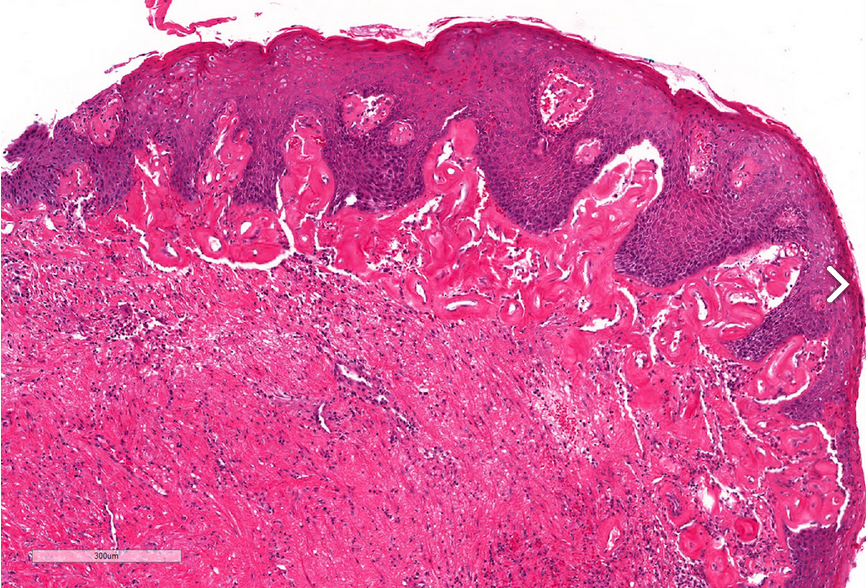

Lichen sclerosis

Normal to atrophic epithelium covering a band of diffuse sclerosis in the lamina propia overlying a dense and continuous band of lymphocytes. Note the vacuolization of basal cells and the globular perivascular hyalinization at the epithelial-stromal interface.